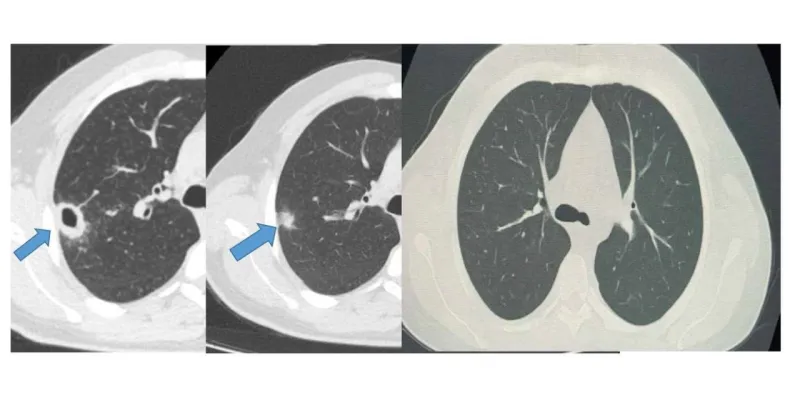

Bayburt Devlet Hastanesi'ne başvuran 50 yaşındaki hasta, öksürük ve balgam şikayetleri üzerine muayene edildi. Göğüs Hastalıkları Uzmanı Uzm. Dr. Hilal Sayma tarafından yapılan muayenede, hastanın akciğerinde kitle benzeri bir doku tespit edildi. Bu durum üzerine derhal ileri tetkiklere başlandı.

Uzm. Dr. Hilal Sayma, hastanın durumunu değerlendirerek bronkoskopi işlemini uygun gördü. Bronkoskopi sonucunda lezyonun kanser veya tüberküloz gibi ciddi hastalıklarla ilişkili olmadığı belirlendi. Bu, hem doktorlar hem de hasta için büyük bir rahatlama oldu. Erken teşhisin ne kadar önemli olduğu bir kez daha kanıtlanmış oldu.

Yapılan tetkikler sonucunda hastanın durumuna uygun bir tedavi planı oluşturuldu. İki haftalık tedavi sürecinin sonunda yapılan kontrollerde, lezyonun neredeyse tamamen gerilediği görüldü. Bu başarılı sonuç, erken teşhisin ve doğru tedavinin ne kadar etkili olduğunu bir kez daha gözler önüne serdi.